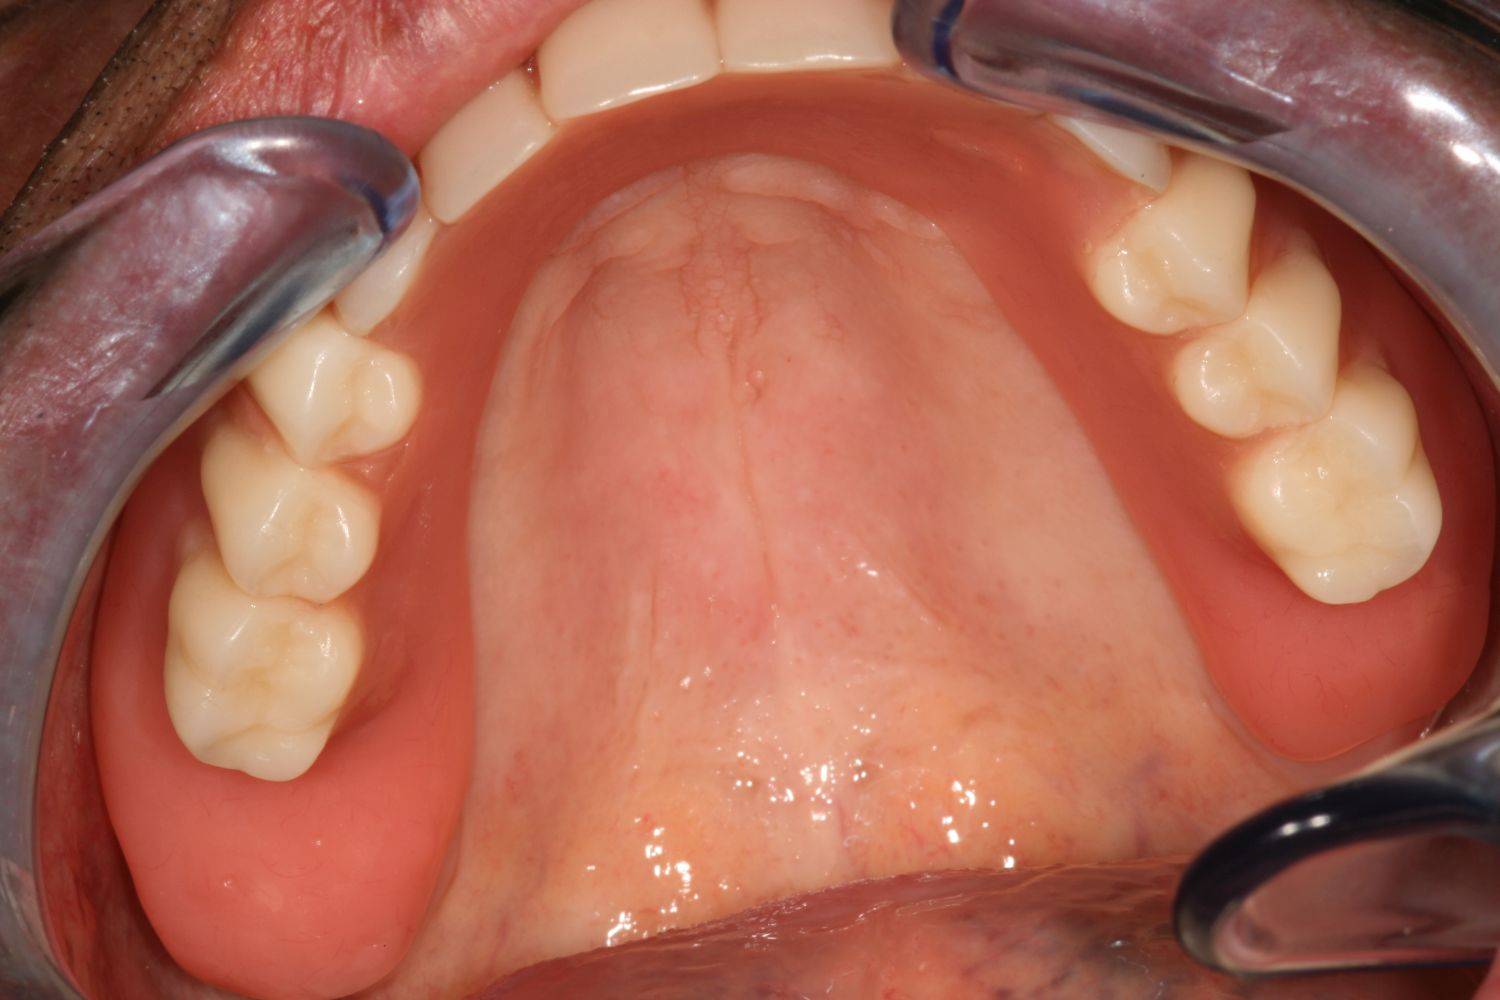

3. eset

4 implantátumra rögzített stéggel stabilizált "Overdenture" megoldás. Költséghatékony módszer fogsorok rögzítésére. Nagyfokú stabilitás érhető el redukált felületeken. Ebben az esetben jól látható, hogy a szájpadlást nem fedi be a kivehető fogsor, az ízlelés is megmarad, mégis javul a rágási képesség és a fogsorok mozgásmentesen rögzülnek.